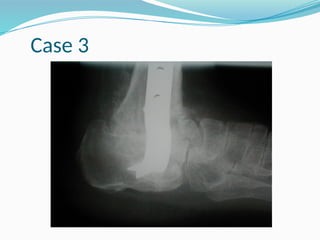

Case 3

DNOAP IV Destruction oftibiotalar joint Lateral malleolar prominence at risk of ulceration

• 87.

DNOAP V Bayonet deformity Lateralskin ulceration risk Destruction of talo- calcaneal joint